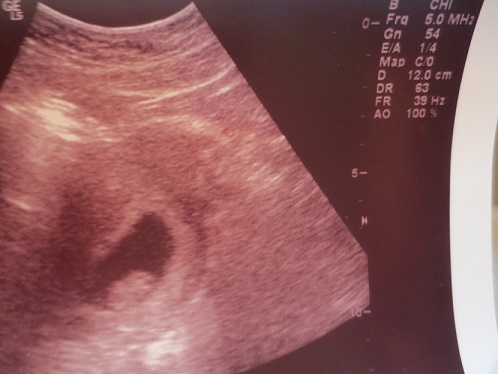

I'm 15 weeks and 3 days pregnant. Based on the skull theory can you tell if boy or girl? Attachment 24143